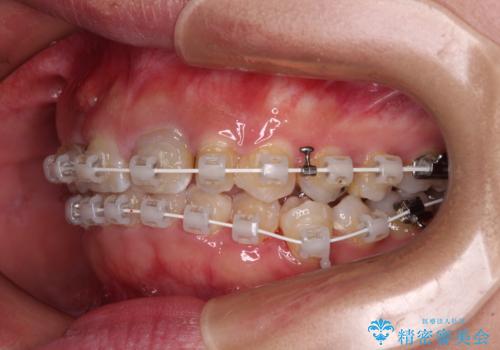

歯列から飛び出た歯 ワイヤー矯正で整った歯列に

- 下顎の歯列から飛び出した小臼歯を気にして来院された患者様です。

歯列以外に、上顎左右側切歯が矮小歯であり、上顎4前歯は失活していたため、矯正治療で歯列を整えるとともに上顎前歯の幅を調整し、矯正治療後にオールセラミッククラウンにて審美歯科治療を行うこととしました。

矯正治療は、小臼歯1本分を歯列に納めないいけない状態であったため、表側のワイヤー装置にて行うこととしました。

下顎の小臼歯を移動しきるのに2年弱の期間を要することとなり、補綴治療も合わせて2年半ほどの治療期間となりました。